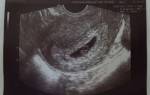

Если проведено УЗИ пациентке детородного возраста, и в малом тазу обнаружена свободная жидкость, а также выявлено вне матки плодное яйцо в окружении кровяных сгустков, скорее всего, врач диагностирует внематочную беременность. Скопление воды вызывают и другие причины, в частности, это болезни различных органов брюшной полости, например, подобная симптоматика может сопровождать болезни печени.

Этот показатель определяется на УЗИ. В полость вводится специальный датчик, благодаря которому на экране отображаются все внутренние органы. Врач может оценить строение матки, посмотреть размеры яичников. Если вещество отсутствует, то оно не визуализируется.

Жидкость в брюшной полости при овуляции – нормальный процесс, осуществляемый при разрыве фолликула и выходе яйцеклетки. Освободившись из капсулы, она направляется навстречу сперматозоидам для оплодотворения. Именно овуляторные процессы могут вызывать появление незначительного количества вещества.

В самом же фолликуле его очень мало, поэтому жидкость за маткой после овуляции является нормой и не должна вызвать чувство тревоги. Через несколько дней она автоматически рассасывается.